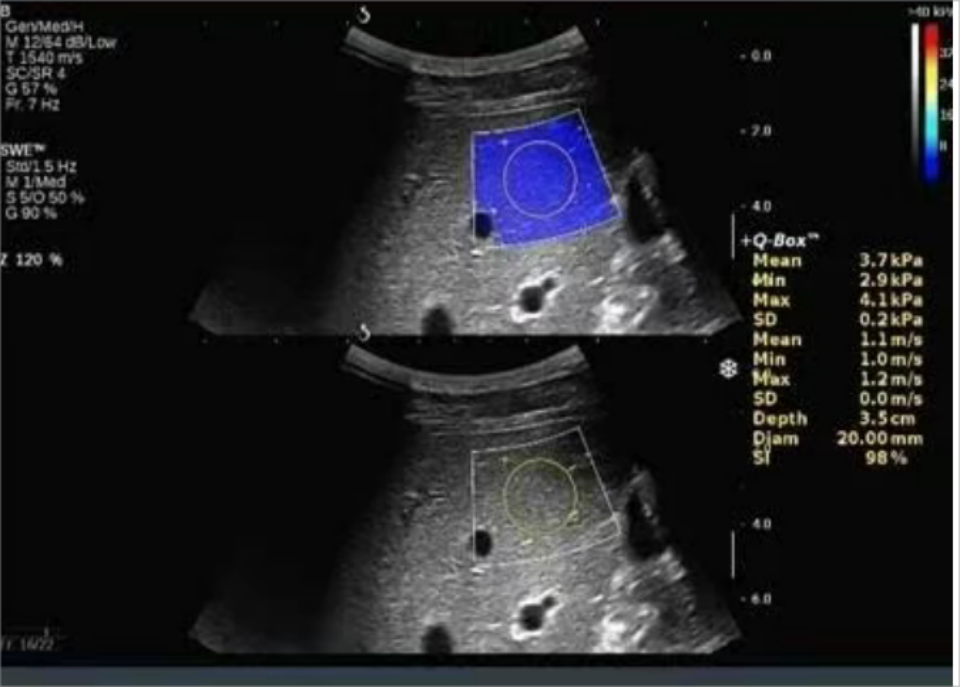

shear wave imaging:剪切波成像技术(SWI)

• 基于ARFI技术

基于ARFI技术衍生的超声剪切波成像,通过调整脉冲激励方式,根据水平方向多个点的位移-时间曲线估算横向传播的剪切波波速,然后利用剪切波传播特性与生物组织弹性特征之间的内在联系,最终定量重构组织的弹性模量以形成二维的图像。

• 技术创新

这一技术克服了声辐射力作用域有限而传统徒手弹性成像无法定量的不足,能定量的观察出更深全域组织部位的病变状况,拓展了探测深度,为临床应用提供更准确的参数指标。

定量弹性成像